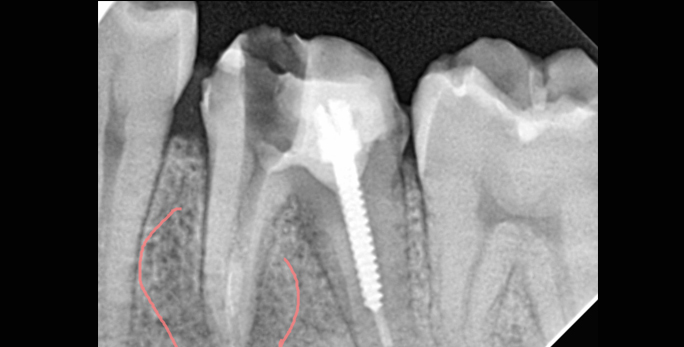

• 심한 치수염으로 타원에서 뿌리뼈 소실로 발치평가 받은 환자 본원에서 치료 후 2개월(깨끗하게 골회복)

• 타원신경치료 실패 후 발치평가 받은 환자 치근단 절제술로 발치하지 않고 부러진 기구 제거 및 치아 보존

• 신경치료한 뿌리 끝에 염증이 크게 번져있는 상태 치료 후 염증 및 통증 소실